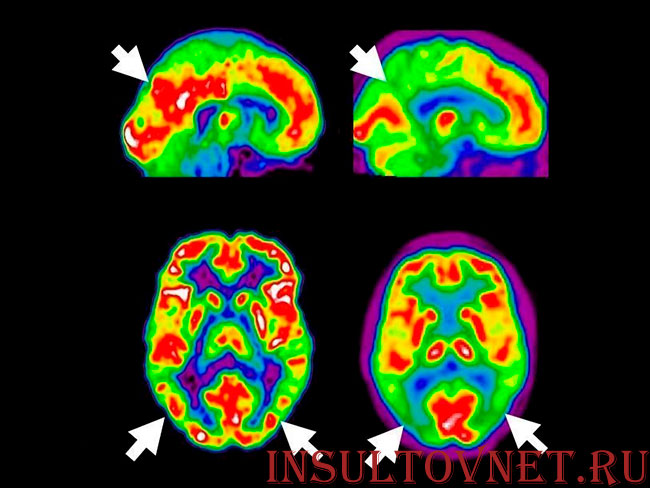

Диагностика при помощи ПЭТ-сканирования является эффективным методом исследования. Питтсбургский состав В вводится в организм, с током крови попадает в мозг и закрепляется за клетки амилоида. В процессе исследования изображение на сканере отражает количество и распространенность амилоида.

- Компьютерная томография

- Магнитно-резонансная томография

- Фотонно-эмиссионная компьютерная томография.

Эти методы исследования помогают отличить болезнь Альцгеймера от других видов деменции.